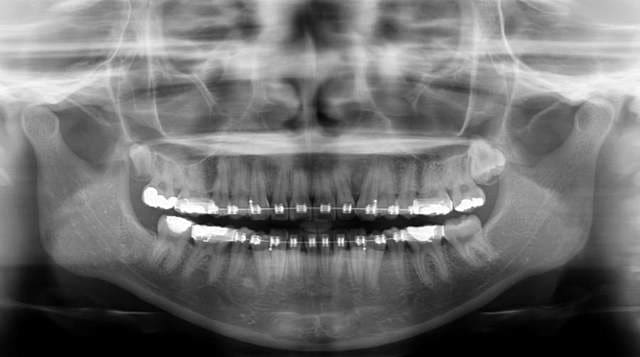

Et voici les radio prise le jour de la réevaluation.

Les condyles sont dans une position plus symmetrique.

L'openbite et l'overjet vont très probablement se regler par intrusion des 7, mais l'apparition du problème et due au non diagnostique de la mauvaise position des ATM